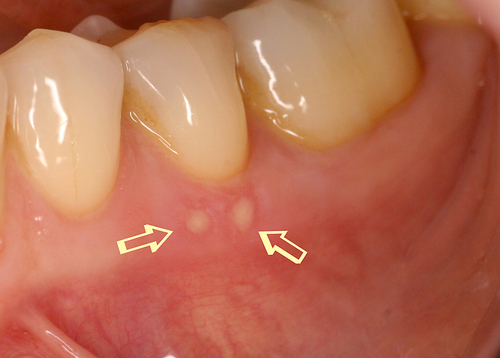

Par exemple, sur des aphtes douloureux (fig. 20) un rayonnement laser est rapproché progressivement jusqu’à une disparition quasi complète des sensibilités (fig. 21).

Fig.20 Présence de deux aphtes douloureux